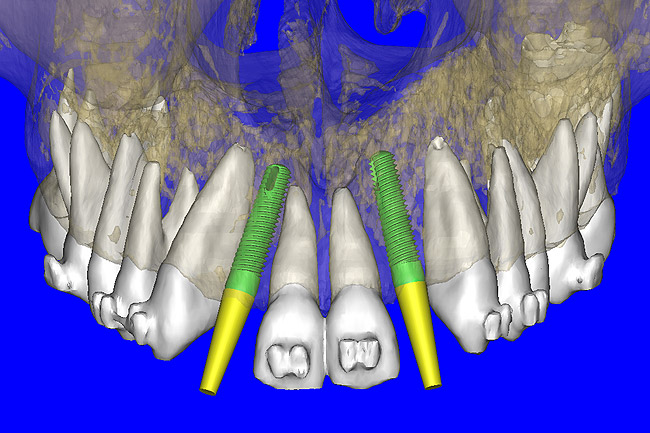

After the basic plan had been established, it was re-evaluated using interactive 3D images. The reconstructed 3D view of the maxilla clearly illustrated the extent of the bilateral facial concavities, and the root eminences of the adjacent and posterior teeth (Figure 7A). The placement of the virtual implants then was evaluated to ensure that the facial cortical plate was not perforated (Figure 7B). The implants were labeled individually as “7” and “10,” with the simulated yellow abutment projection indicating the facial-lingual inclination through the bone to the level above the incisal edge of adjacent teeth. The ability to gain a better understanding of these individual root forms can not be underestimated. The dental literature has suggested certain parameters for placing implants near teeth and implants next to other implants. However, there is little scientific 3D documentation to support these suggested rules.5-10 The use of an interactive treatment-planning software application permits closer scrutiny of previously difficult-to-visualize areas, and can now be used to redefine perceptions of spatial positioning of implants, especially when in close proximity to natural tooth roots, vital anatomy, and adjacent implants.27-29

Figure 7a  The 3D reconstruction showed (A) the facial concavities and root eminences, and allowed (B) for evaluation of virtual implant placement to ensure the facial cortical plate was not perforated.

Figure 7a

Figure 7b  The 3D reconstruction showed (A) the facial concavities and root eminences, and allowed (B) for evaluation of virtual implant placement to ensure the facial cortical plate was not perforated.

Figure 7b